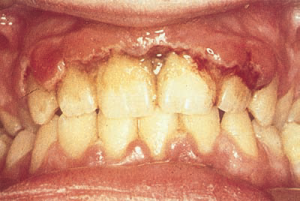

Анамнез: профессия больного (характер производства, длительность работы на нем), перенесенные заболевания и болезни в настоящее время, их лечение и связь с заболеванием пародонта, наличие вредных привычек, характер питания и его регулярность; уровень гигиенических навыков по уходу за полостью рта (регулярность чистки зубов, вид зубной щетки, наименование средства гигиены), состояние полости рта у родственников, так как существует мнение о наследственном факторе в развитии патологии пародонта. Необходимы общий осмотр больного, оценка общего и эмоционального состояния, контактности больного. Важное значение имеет непосредственный осмотр полости рта: состояние зубов и слизистой оболочки, уздечек губ, языка и их прикрепления; состояние десневого края (цвет, консистенция, экссудат, атрофия или гипертрофия, изъязвления, свищи, абсцессы, распространенность процесса, наличие зубодесневых карманов), наличие зубного налета и зубного камня (наддесневые, поддесневые, плотные, мягкие, обильные, умеренные); оценка окклюзии (вид прикуса, локализации функциональной перегрузки), вид и состояние зубных протезов. Глубина зубодесневых карманов определяется специальным градуированным зондом с четырех поверхностей зуба, характер и количество экссудата определяется визуально или по площади обесцвечивания йодинола нанесенного на стандартные полоски фильтровальной бумаги. Подвижность зубов (три степени) выявляется с помощью зубоврачебного пинцета, а степень вовлечения пульпы в общий процесс с помощью электроодонтометрии.